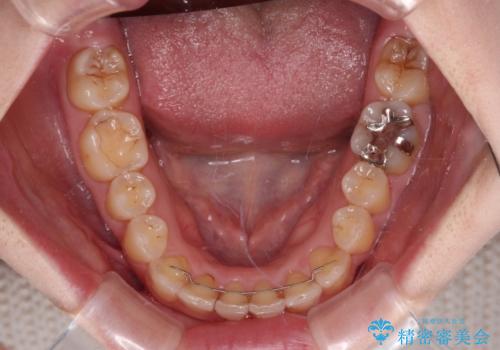

補助装置だけでなく、部分的にワイヤー矯正も使用しましたが、上下のスペースは改善しきれず、側切歯(前から2番目の歯)や顕著な八重歯は、インビザラインで治療するには限界があることがよく分かりました。

より良い仕上がりを希望される場合には、ワイヤー装置による矯正治療がお勧めとなります。